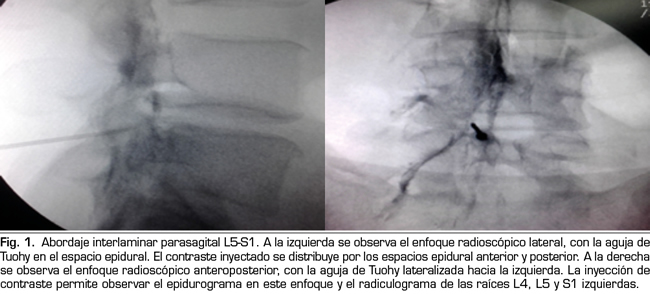

Los procedimientos fueron realizados en sala de operaciones. Con el paciente en posición decúbito ventral se colocó una vía venosa periférica. La asepsia se efectuó con clorhexidina alcohólica y la anestesia local con lidocaína al 0,5 %. En la técnica interlaminar parasagital se utilizaron agujas de Tuohy números 18, 3½ o 4¾ pulgadas según la complexión física del paciente. Con enfoque radioscópico anteroposterior, se introdujo la aguja en los espacios interlaminares, L4/L5 o L5/S1, utilizando la técnica en visión túnel, parasagital homolateral del lado correspondiente al dolor radicular (Figura 1). Se realizó pérdida de resistencia con suero fisiológico. En el enfoque lateral se administró una inyección de 4 ml de contraste (Omnipaque®) y se consignó la presencia de epidurograma anterior, posterior o ambos (Figura 1). En el enfoque anteroposterior se consignaron las características del radiculograma y del epidurograma (Figura 1). Luego se administró un frasco de betametasona (12 mg de una mezcla de fosfato y acetato de betametasona, en 2 cc de solución) más 3 cc de lidocaína al 0,5 % (total 5 cc de solución). Se evaluó la calidad técnica del bloqueo con elementos clínicos como la presencia de parestesias o dolor concordante durante la inyección, y datos radiológicos como la presencia de radiculograma y de epidurograma anterior (Figura 1). En el grupo tratado con betametasona por vía epidural transforaminal se utilizaron agujas de Quincke números 22, 3½ o 4¾ pulgadas con enfoques radiológicos oblicuo, lateral y anteroposterior. El punto objetivo en posición oblicua fue la zona subpedicular, en enfoque lateral el ángulo anterosuperior o techo del neuroforamen, en el llamado triángulo de seguridad en el enfoque anteroposterior (Figura 2). La inyección de contraste fue equivalente a la realizada en el grupo interlaminar, debiéndose obtener radiculograma y epidurograma tras la inyección (Figura 2). La solución de betametasona fue la misma que la utilizada en el grupo interlaminar, inyectándose la totalidad de la solución por el neuroforamen elegido, o la mitad de la solución en cada neuroforamen cuando por criterios clínicos se decidió la inyección en dos niveles.

En 21 de los 26 procedimientos realizados por el acceso interlaminar parasagital se evaluó la calidad técnica de la inyección epidural de esteroides. En 15 (71 %) se obtuvo epidurograma anterior, esto es, alcance de la solución en la cara ventral del espacio (Figura 1 izda.); en 17 (85 %) el paciente refirió dolor o parestesias en el territorio radicular durante la inyección, y en 12 (60 %) se observó radiculograma junto a la imagen característica de epidurograma.